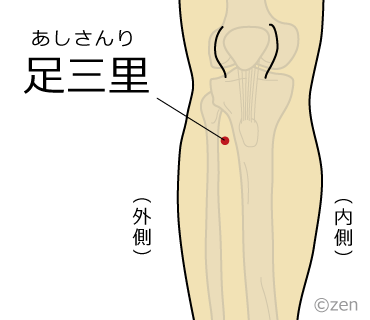

足三里

足のすねの外側、膝の皿(膝蓋骨)のくぼみから指4本分下に位置するツボです。

足の万能穴と呼ばれ、冷えや足のしびれ、腹痛など様々な症状に効果が有ります。